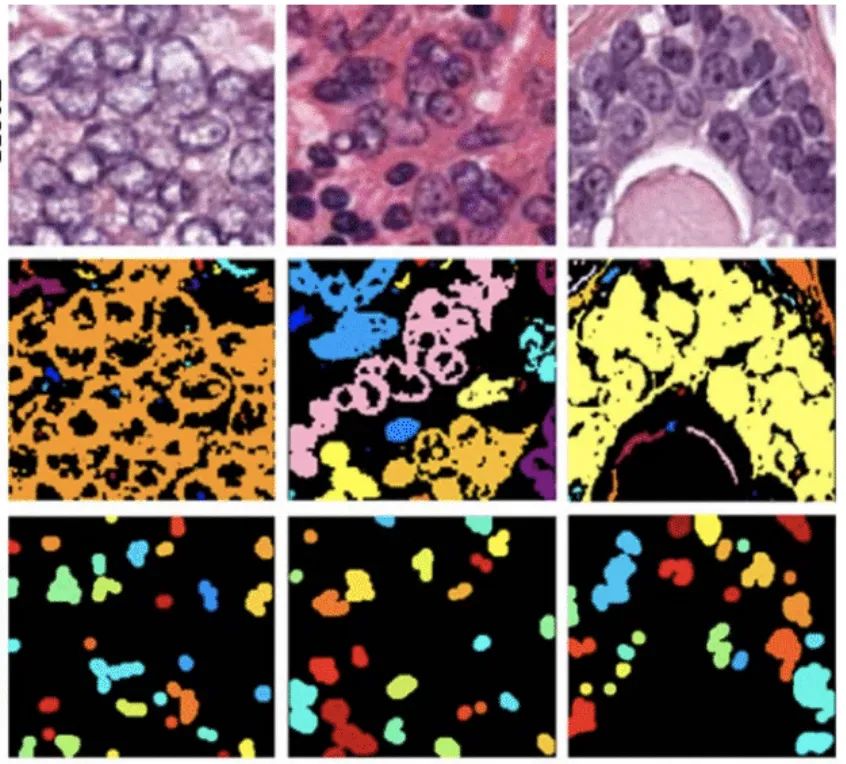

肿瘤数据集

数据集链接:http://m6z.cn/5zCyGj

这一数据集是通过仔细注释几名患有不同器官肿瘤并在多家医院被诊断出的患者的组织图像获得的。该数据集是通过从TCGA存档下载以 40 倍放大倍率捕获的 H&E 染色组织图像创建的。H&E 染色是增强组织切片对比度的常规方案,通常用于肿瘤评估(分级、分期等)。考虑到多个器官和患者的细胞核外观的多样性,以及多家医院采用的丰富染色方案,训练数据集将能够开发出开箱即用的稳健且可推广的细胞核分割技术。